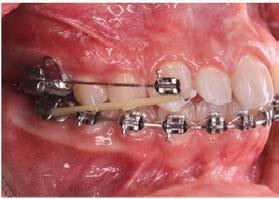

Por lo que se propone procedimiento quirúrgico con la evidente comunicación oroantral al realizar las extracciones de los órganos dentales involucrados. Previa asepsia y antisepsia, colocación de campos estériles, extracción de segundo y tercer molar superior derecho e incisión envolvente con descarga mesial (Figura 3), rotación y afronte mediante puntos simples de la bola adiposa de Bichat para el cierre de la comunicación oroantral (Figura 4), farmacoterapia con base en amoxicilina con ácido clavulánico. Una semana después refiere no presentar rinorrea y mejoría al 100% de la obstrucción. Posterior a 6 meses de evolución clínica (Figura 5) y radiográficamente (Figura 6), no se observa comunicación oroantral o paso de líquidos de la cavidad oral a la cavidad nasal.

Figura 3. Colgajo envolvente con liberatriz mesial y alveolo postextracción.